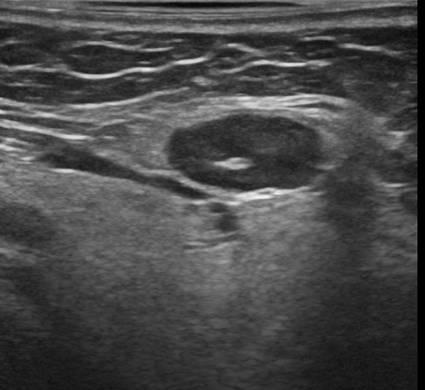

Hạch tuyến nước bọt

» Thông tin: Nữ giới – 66 tuổi.

» Lâm sàng: Sưng đau vùng góc hàm.

# Hạch lành tính ngoại vi tuyến nước bọt dưới hàm.